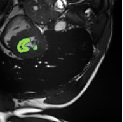

Despite their outstanding accuracy, semi-supervised segmentation methods based on deep neural networks can still yield predictions that are considered anatomically impossible by clinicians, for instance, containing holes or disconnected regions. To solve this problem, we present a Context-aware Virtual Adversarial Training (CaVAT) method for generating anatomically plausible segmentation. Unlike approaches focusing solely on accuracy, our method also considers complex topological constraints like connectivity which cannot be easily modeled in a differentiable loss function. We use adversarial training to generate examples violating the constraints, so the network can learn to avoid making such incorrect predictions on new examples, and employ the Reinforce algorithm to handle non-differentiable segmentation constraints. The proposed method offers a generic and efficient way to add any constraint on top of any segmentation network. Experiments on two clinically-relevant datasets show our method to produce segmentations that are both accurate and anatomically-plausible in terms of region connectivity.